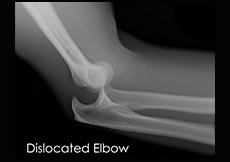

Elbow Dislocation

The arm in the human body is made up of three bones that join to form a hinge joint called the elbow. The upper arm bone or humerus connects from the shoulder to the elbow to form the top of the hinge joint.